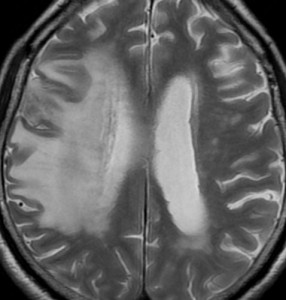

手術後の脳浮腫の改善

手術で放射線壊死巣を摘出してから1月半後のMRIです。放射線壊死が摘出されて,脳浮腫もかなり改善しました。同時に右麻痺もよくなってきました。

この例では,アバスチンを投与するという選択肢もあったのですが,医療費が高額で患者さんが経済的に耐えられません。